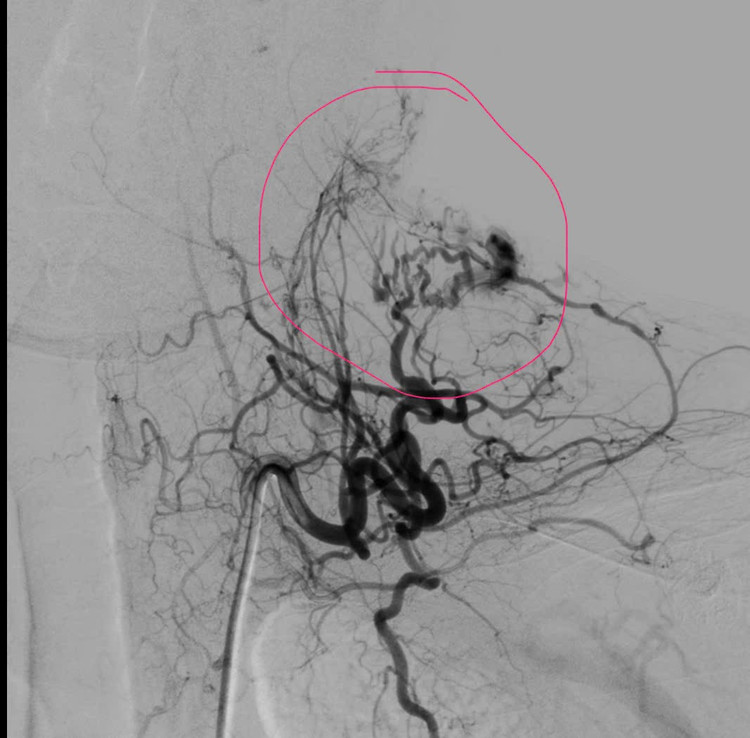

Qua thăm khám lâm sàng kết hợp chụp MSCT, các bác sĩ ghi nhận ổ dị dạng động – tĩnh mạch (AVM) dạng nidus lan tỏa nằm ở phần mềm dưới da vùng cổ. Trước tính chất phức tạp của tổn thương, người bệnh nhanh chóng được hội chẩn đa chuyên khoa, thống nhất chỉ định chụp mạch số hóa xóa nền (DSA) và can thiệp nút mạch cầm máu.

Kết quả chụp DSA cho thấy ổ dị dạng được nuôi dưỡng bởi nhiều cuống mạch xuất phát từ thân giáp cổ, kèm theo hệ tĩnh mạch dẫn lưu nông giãn lớn lan vùng cổ, vai, lưng, làm tăng nguy cơ chảy máu tái phát nếu không xử trí triệt để.

Dưới hướng dẫn hình ảnh chính xác, ê-kíp đã tiến hành nút tắc chọn lọc từng cuống mạch nuôi bằng keo sinh học, giúp giảm rõ rệt dòng chảy trong ổ dị dạng. Sau can thiệp, người bệnh được khâu vết rách da, băng ép tại chỗ, tình trạng chảy máu cơ bản được kiểm soát hoàn toàn. Toàn trạng ổn định, người bệnh được chuyển về Hồi sức cấp cứu để tiếp tục theo dõi sát.